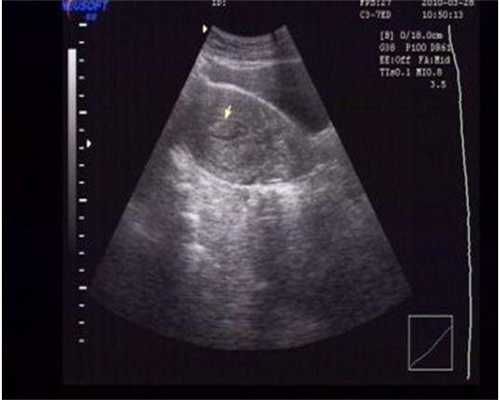

深圳子宫畸形供卵代怀价位但程序很严格形成胚胎价位用早早孕试纸就能测出弱阳性了请郑某夫妇用黑B超看看。